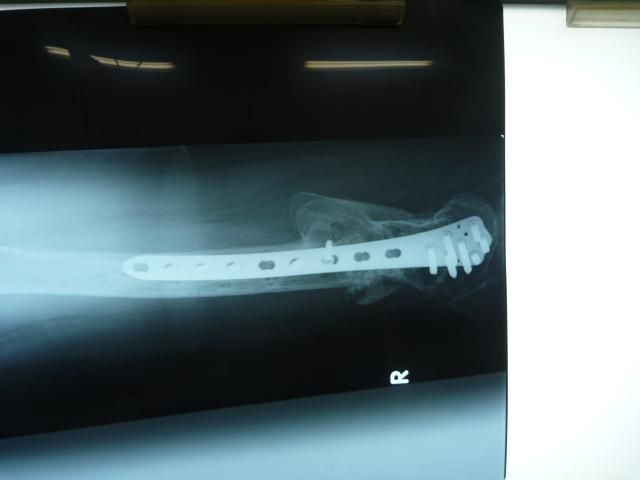

µ×¡¹¤Î¥ì¥ó¥È¥²¥ó

º£Ç¯¤Î¼ê½Ñ¤ÎͽÄê¤ò·è¤á¤ë¥ì¥ó¥È¥²¥ó¤ò»£±Æ¤·¤Þ¤·¤¿¡£

ΩÇɤʤªÊõ¤¬¼Ì¤Ã¤Æ¤Þ¤¹¤¬¡¦¡¦¡¦

¿Ç»¡·ë²Ì¤Ï¡¦¡¦¡¦

¡Ö¹ü¤Ï¿ïʬ¤·¤Ã¤«¤ê¤·¤Æ¤¤Æ¤¤¤ë¤±¤É

¤â¤¦¾¯¤·ÍͻҤò¸«¤è¤¦¤«¡¦¡¦¡¦¡×

¤È¸À¤¦»ö¤Ë¤Ê¤ê¤Þ¤·¤¿¡£

´°Á´¤Ë¹ü¤¬½ÐÍè¾å¤¬¤Ã¤Æ¤Þ¤¹¡£

¤³¤Î¥×¥ì¡¼¥È¤ò¼è¤ë»þ¤Ë

¤â¤¦¾¯¤·¶Ê¤²¤ì¤ëÍͤˤʤë¤Ï¤º¤Ç¤¹¡£

ΩÇɤʤªÊõ¤¬¼Ì¤Ã¤Æ¤Þ¤¹¤¬¡¦¡¦¡¦¿Ç»¡·ë²Ì¤Ï¡¦¡¦¡¦

´°Á´¤Ë¹ü¤¬½ÐÍè¾å¤¬¤Ã¤Æ¤Þ¤¹¡£¤³¤Î¥×¥ì¡¼¥È¤ò¼è¤ë»þ¤Ë